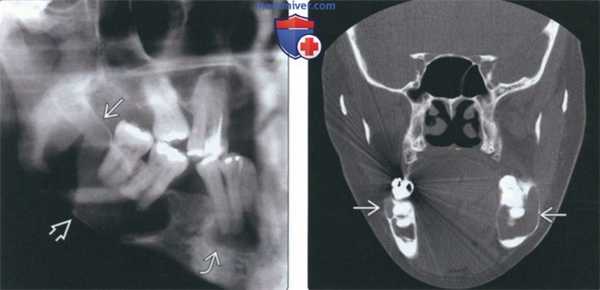

(Слева) Обратите внимание на ПКД с включениями цемента с обеих сторон. Крупное просветление с иаонченной и приподнятой кортикальной пластинкой справа обусловлено вторичной костной кистой. Широкие просветления с истонченными и приподнятыми кортикальными пластинками слева - другие простые костные кисты.

(Справа) На периапикальной рентгенограмме в передних отделах нижней челюаи определяется зрелая ЦКД. Округлые затемнения окружены тонкими линейными просветлениями, что позволяет отличить ЦКД от болезни Педжета.